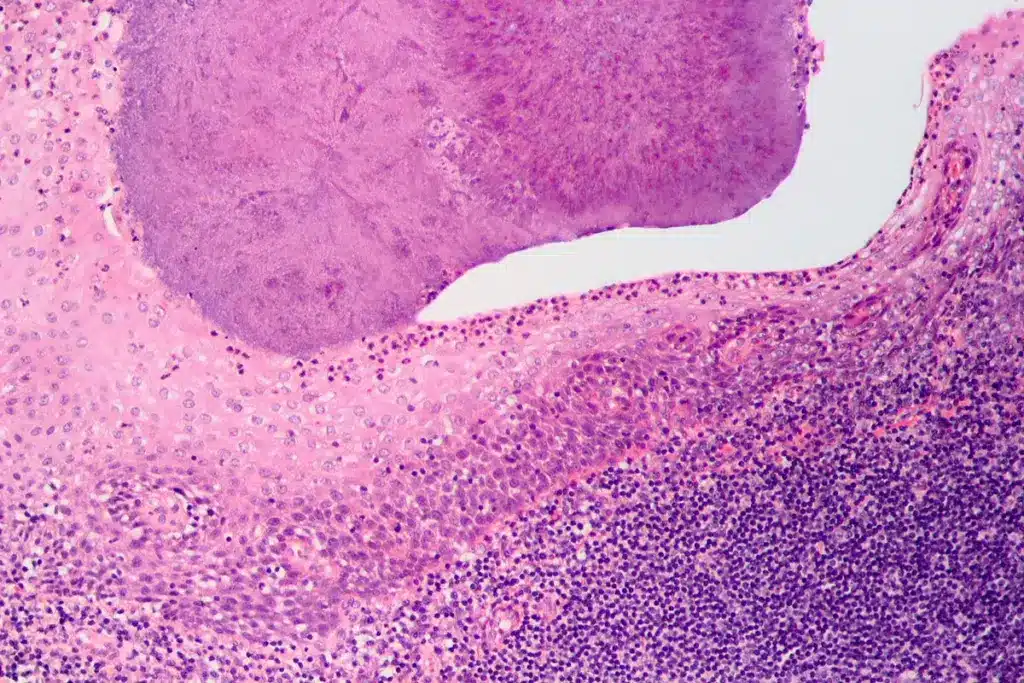

Visual Clues: What Your Throat Reveals

Looking closely at your throat can show important signs. These signs help tell if you have bacterial or viral tonsillitis. Knowing this is key to finding the right treatment.

Appearance of Tonsils in Bacterial Infections

Bacterial tonsillitis shows up with more inflammation and pus. Your tonsils might look swollen, red, and have white or yellow spots.

At times, bacterial infections can make tonsils so big they touch. This is called “kissing tonsils.” It can make breathing and swallowing hard.

Appearance of Tonsils in Viral Infections

Viral tonsillitis causes less inflammation than bacterial. Your tonsils might be red and swollen, but you won’t see pus. You might also have a runny nose or cough.

In viral infections, your throat looks red and inflamed. But, your tonsils won’t have the white or yellow patches seen in bacterial infections.